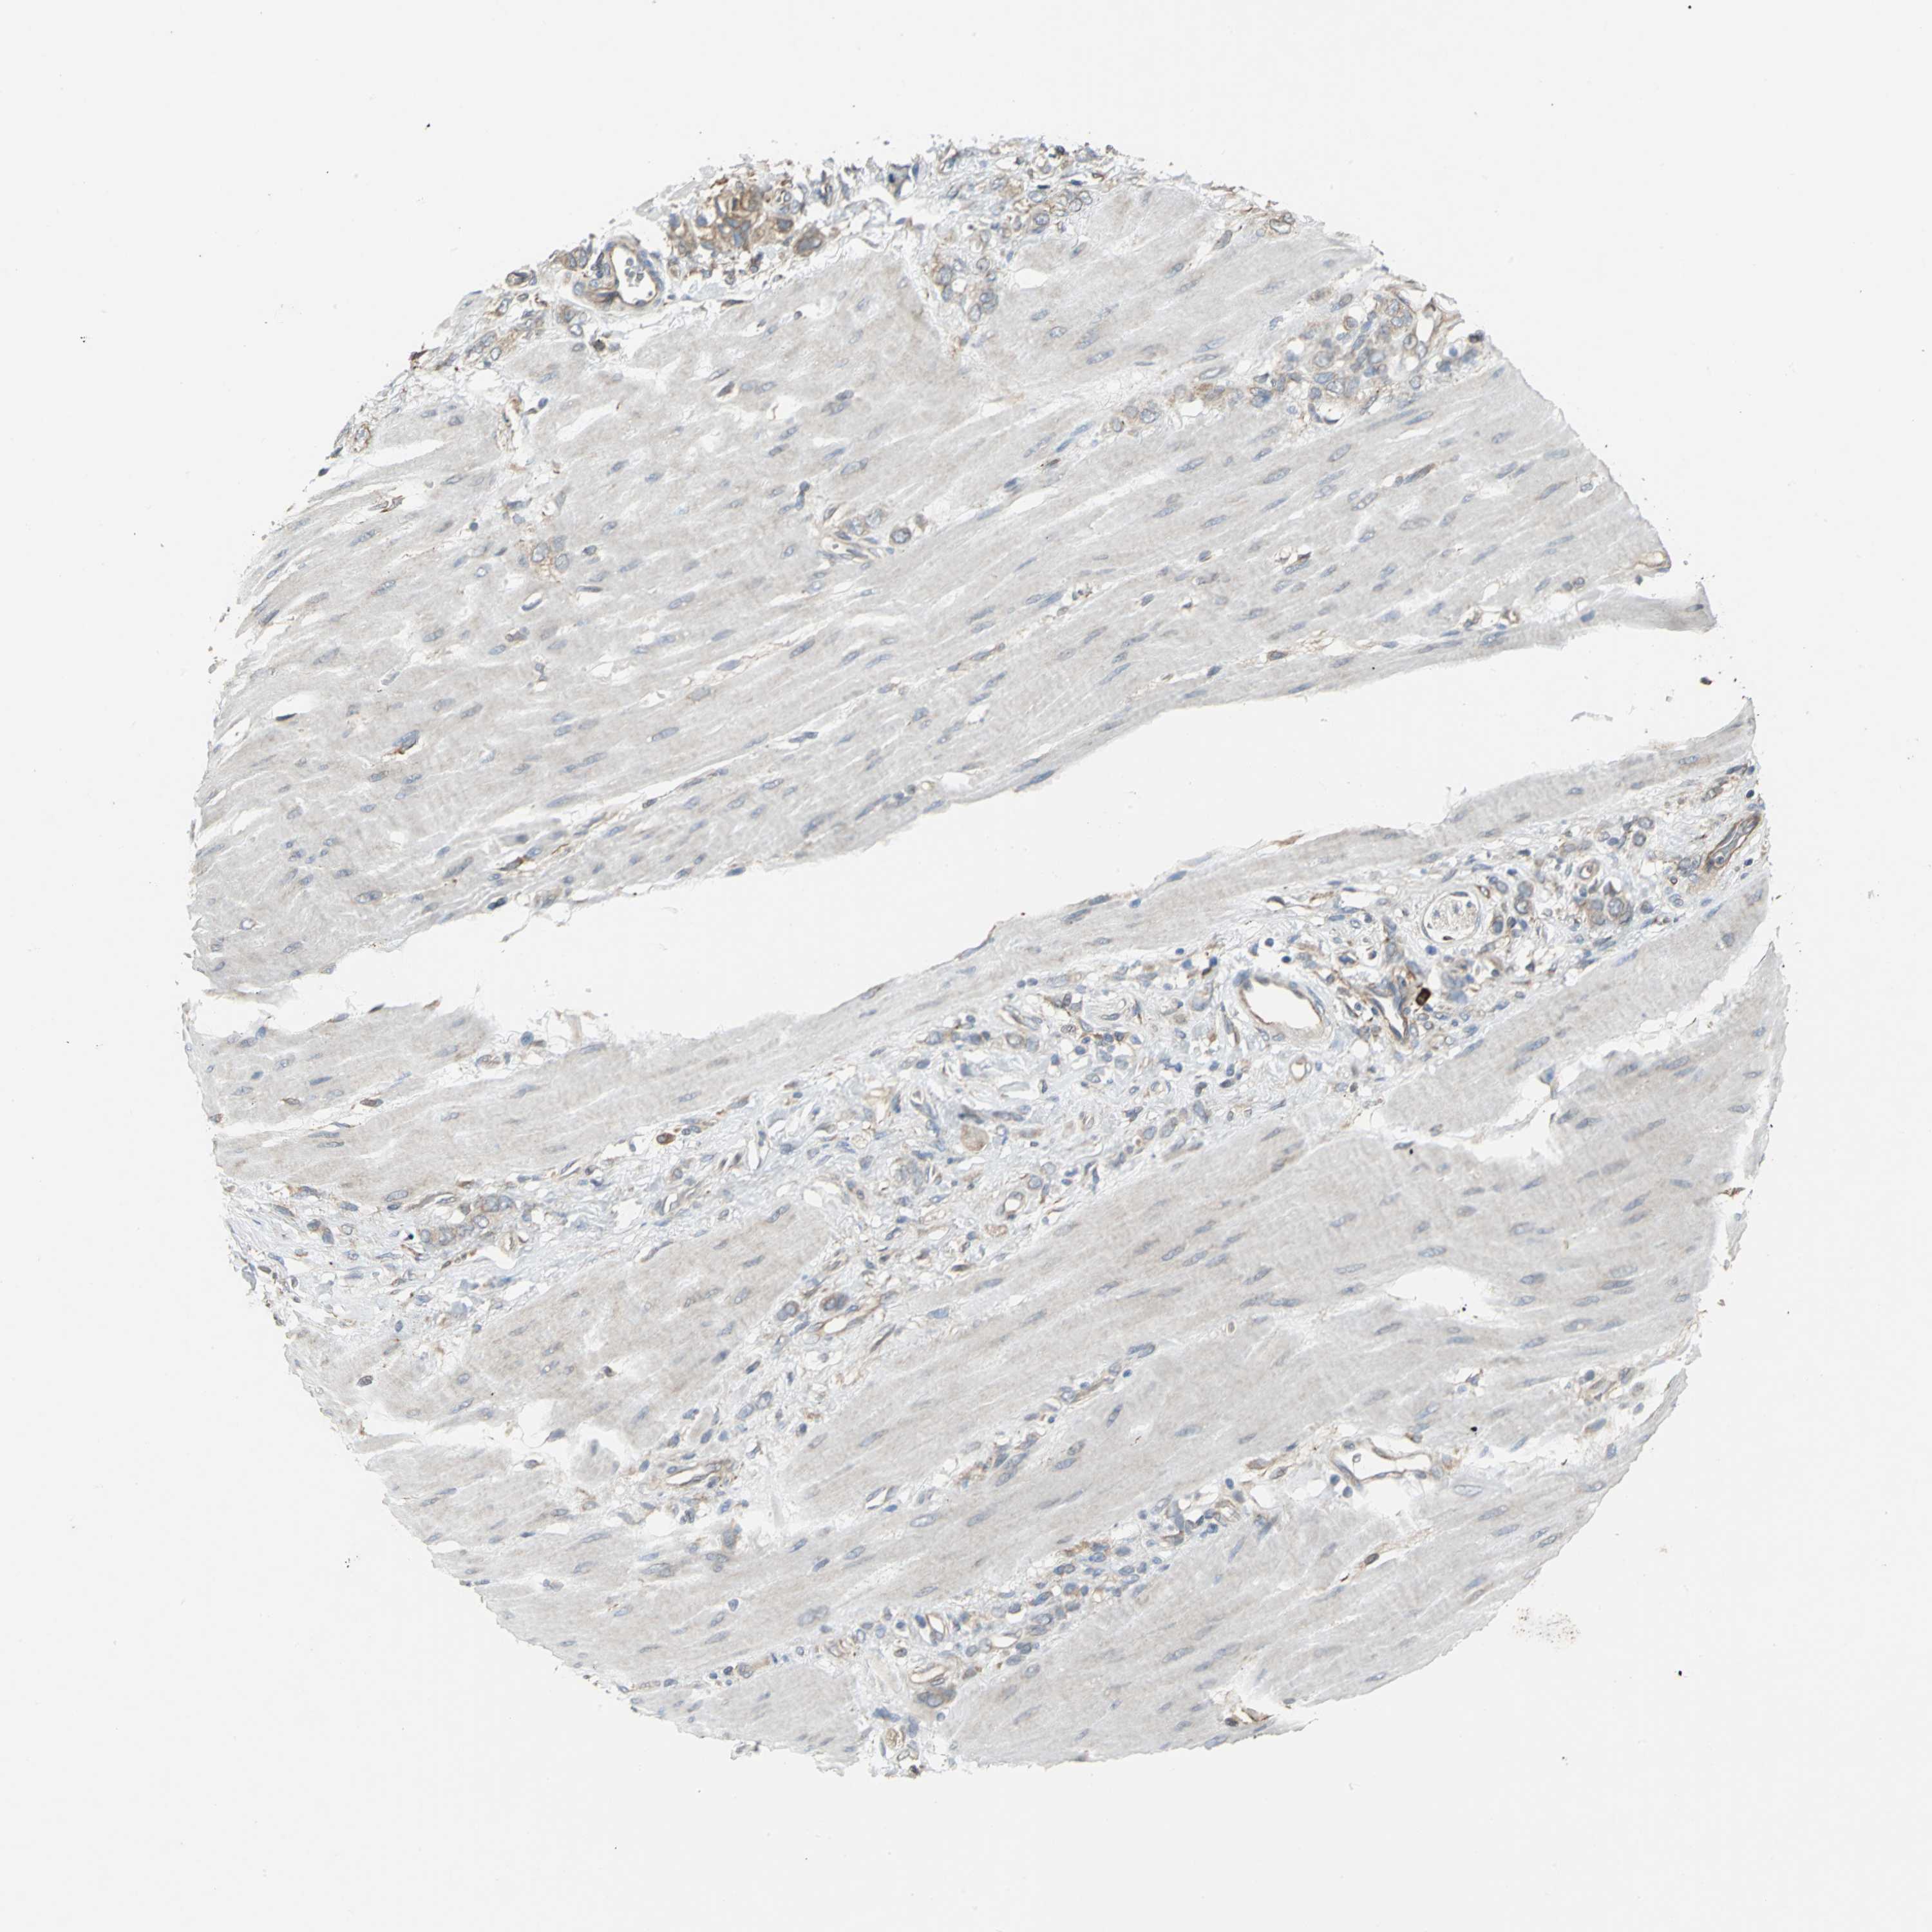

STOMACH CANCER - Protein expressioni

A mouse-over function shows sample information and annotation data. Click on an image to view it in a full screen mode. Samples can be filtered based on level of antibody staining by selecting one or several of the following categories: high, medium, low and not detected. The assay and annotation is described here.

Note that samples used for immunohistochemistry by the Human Protein Atlas do not correspond to samples in the TCGA dataset.

Antibody stainingi

Antibody staining in the annotated cell types in the current human tissue is reported as not detected, low, medium, or high, based on conventional immunohistochemistry profiling in selected tissues. This score is based on the combination of the staining intensity and fraction of stained cells.

Each image is clickable and will lead to virtual microscopy that enables deeper exploration of all samples and also displays staining intensity scores, fraction scores and subcellular localization as well as patient and tissue information for each sample.

Antibody HPA005480

Antibody HPA024300

Antibody CAB037030

Staining

High

Medium

Low

Not detected

Intensity

Strong

Moderate

Weak

Negative

Quantity

>75%

75%-25%

<25%

None

Location

Nuclear

Cytoplasmic/membranous

Cytoplasmic/membranous,nuclear

Adenocarcinoma, NOS

Adenocarcinoma, High grade